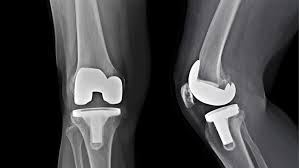

Kalça protezi sonrası fizyoterapi

İleri yaşta, genellikle düşme sonrası kırıkların ted.